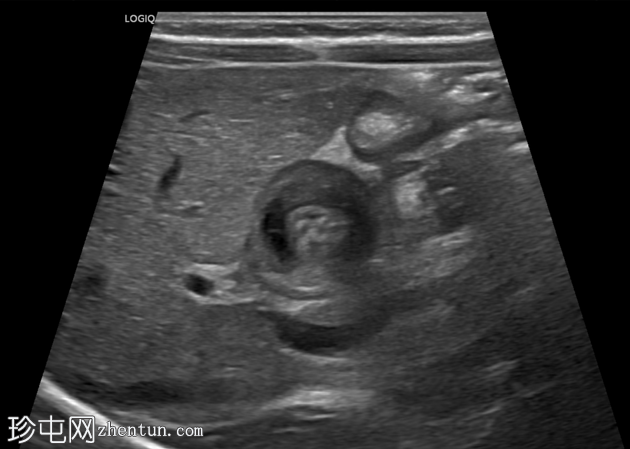

超声

检查

斜位

幽门管明显增厚,测量结果如下:

单层肌肉厚度约5毫米

管径约15毫米

管长约20毫米

横位图像显示幽门管狭窄的靶征。

总体测量结果提示肥厚性幽门狭窄。